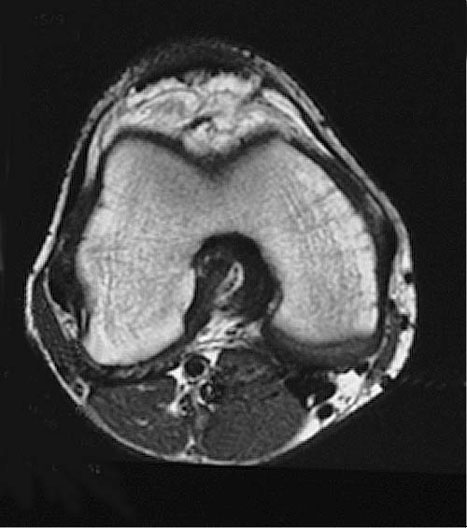

Knee MRI Cross Section

Roll mouse over image to display labels.

1. Anterior cruciate ligament

2. Posterior cruciate ligament

3. Lateral head of gastrocnemius

4. Medial head of gastrocnemius